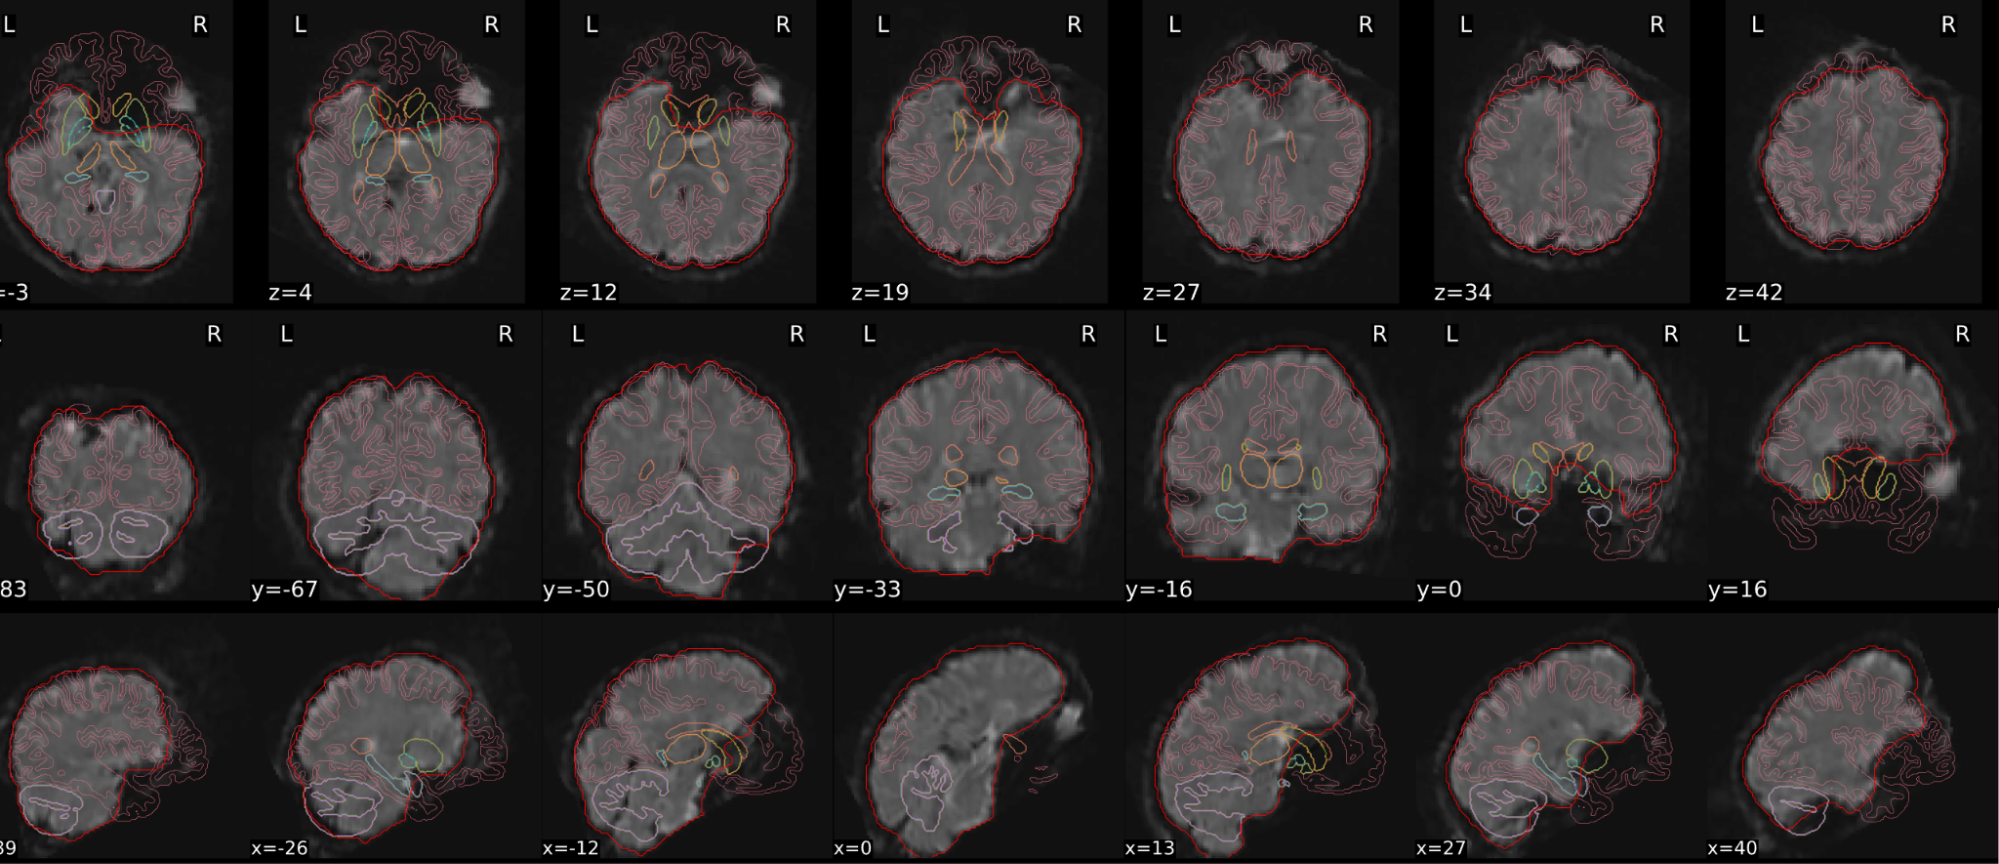

EPI spatial normalisation

This QC step shows the registration of the EPI image to MNI space.

Example of a good subject

- If the registration performed well, you should see an overlap (i.e., correspondence of structures) between the MNI template and the EPI registered to the MNI space.

- If parts of the brain are missing due to the scanner field of view, this is fine. For example, the cerebellum may be cut off for a participant with a large head.

Example of a bad subject

- In case of poor registration, you should see a misalignment of the EPI and the MNI template

Summary

| good | bad |

|---|---|

| Overlap (i.e. match of structures) between the MNI template and the EPI registered in the MNI space | Misalignment of the EPI and the MNI template |

| If parts of the brain are missing because the field of view of the scanner is limited, the EPI spatial normalisation does not have to be excluded e.g. cerebellum cut off in person with large head |

If parts of the brain are missing because the field of view of the scanner is limited, the EPI spatial normalisation does not have to be excluded (e.g. cerebellum cut off in person with large head)